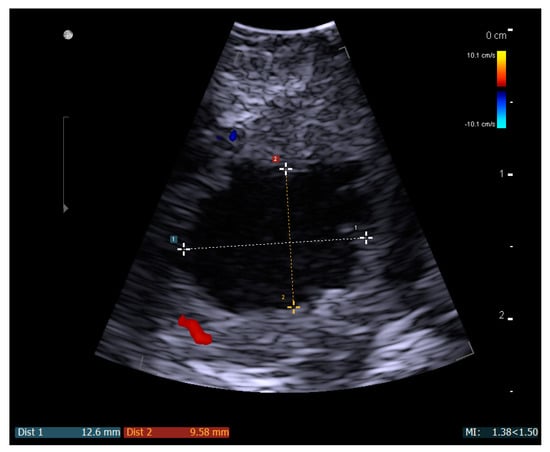

A Novel Technique for Intraoral Ultrasound-Guided Aspiration of Peritonsillar Abscess

2. Materials and Methods

3. Results